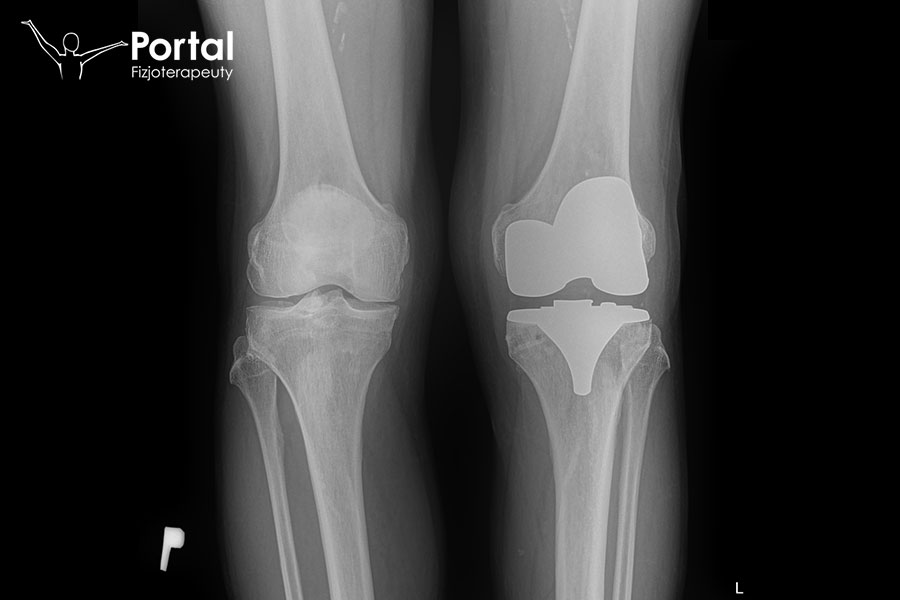

Endoprotezoplastyka

Endoprotezoplastyka to zabieg polegający na wymianie zniszczonego procesem chorobowym stawu na sztuczny, w pełni sprawny, mający przywracać biomechanikę ruchu. Najczęściej